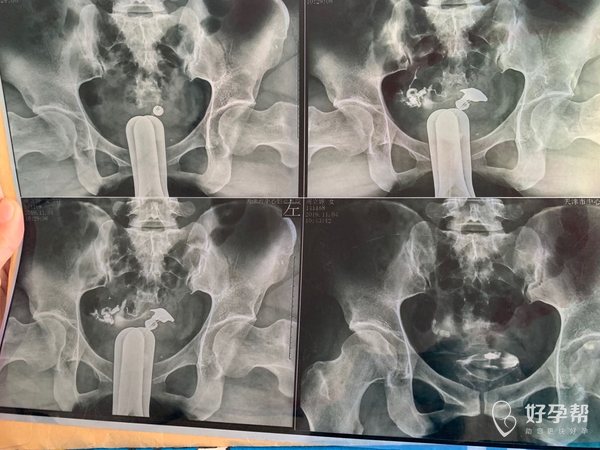

我今年34岁,右侧输卵管粘连,左侧宫外孕输卵

这种必须做手术么还是取了胚胎不是非要做

这个手术不是非得要马上做,需要根据你的年龄、生育计划等来综合评估并权衡利弊后再决定是否需要手术以及什么时候做。如果是做试管通常为了避免输卵管积液及炎症因子逆流至宫腔影响胚胎着床等,会行输卵管结扎等手术,这个手术通常在移植前完成